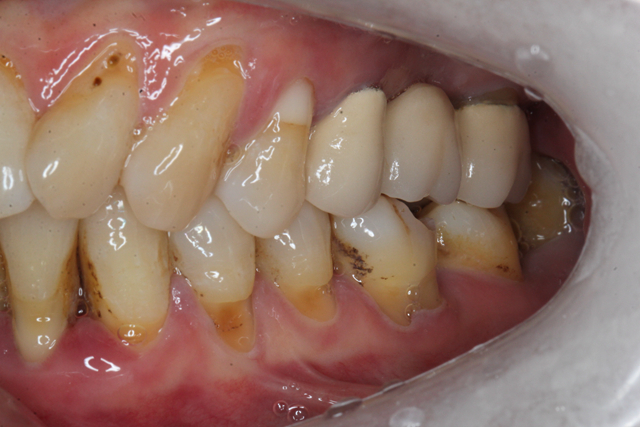

牙齿对于机体来说十分重要,对饮食以及内脏功能都会造成影响。在刷牙和进食时牙齿容易出现酸软的情况,通常是由于有龋齿、牙齿不正、牙周炎、牙龈萎缩等造成的。

1、龋齿:在日常饮食中没有做到按时刷牙,食物长期累积在牙齿中很容易造成龋齿,龋齿是导致牙齿酸软的常见原因之一。主要是由于牙髓神经暴露容易受到外界刺激,引起牙酸不适。了解更多德伦口腔龋齿治疗案例>>>

3、牙周炎:通常牙周炎的患者在早晨刷牙时会出现出血的现象,同时在咀嚼东西时会出现酸痛感,而且牙龈也有红肿的现象。了解更多德伦口腔牙周炎治疗案例>>>

4、牙龈萎缩:生理性萎缩和病理性萎缩现象都会导致牙齿出现酸软的症状。这主要是由于牙周神经末梢极易受到冷、热等不良物理因素刺激导致的。